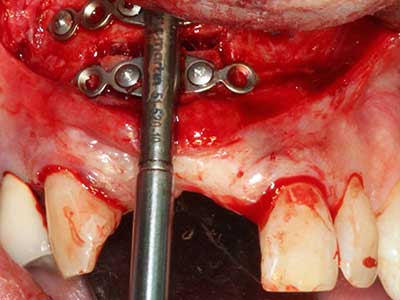

Fig. 18: Preparación de una tapa cortical con la sierra ósea piezoeléctrica (Piezomed, W&H).

Fig. 19: Zona operada después de neurolisis y eliminación del osteomo.

Fig. 20: La tapa ósea extraída se readapta y se fija mediante un tornillo para osteosíntesis (KLS Martin, Tuttlingen).